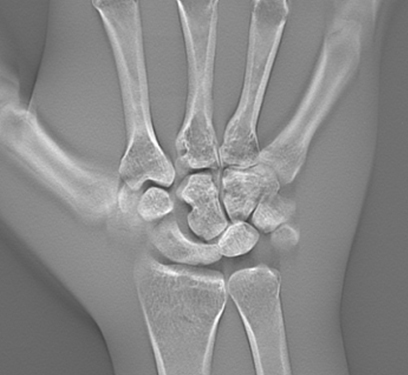

Eine der neuen Funktionen ist die „High Definition“ oder hochauflösende Tomosynthese. Da hier ein großes Datenvolumen verarbeitet wird, werden die Originaldaten auf dem Röntgendetektor mit 2x2-Binning aufgezeichnet, um die Verarbeitungszeit zu reduzieren und das endgültige Tomosynthesebild schneller auf dem Monitor anzuzeigen. Mit der neuesten Bildgebungstechnologie von Shimadzu ermöglicht nun die „HD Tomosynthese“ die Rekonstruktion des Tomosynthesebilds aus Originalbildern, die im hochauflösenden 1x1-Modus mit einem 15 cm großen Sichtfenster gewonnen werden. Dieser neue Modus liefert Bilder mit noch größerer räumlicher Auflösung und ist sehr effektiv bei der detaillierten Diagnose kleiner Bereiche wie der Knochen in den Fingerspitzen oder zur Erkennung von Mikro-Frakturen.

Hochaufgelöste Aufnahmen mit minimalen metallischen Artefakten

Die Kombination aus hochauflösendem Flachdetektor und fortschrittlicher Bildgebung liefert Tomosynthese-Aufnahmen mit hervorragender Bildauflösung, die beispielsweise bei der Diagnose von Mikro-Frakturen sehr geschätzt wird.

Ein weiterer klinischer Vorteil liegt darin, dass die Tomosynthese-Aufnahmen nur minimal durch metallische Artefakte beeinflusst werden, die üblicherweise auf CT-Aufnahmen zu sehen sind. Daher ist die Tomosynthese heute in der Orthopädie insbesondere zur Folgediagnose von Patienten mit Metallimplantaten bestens geeignet.